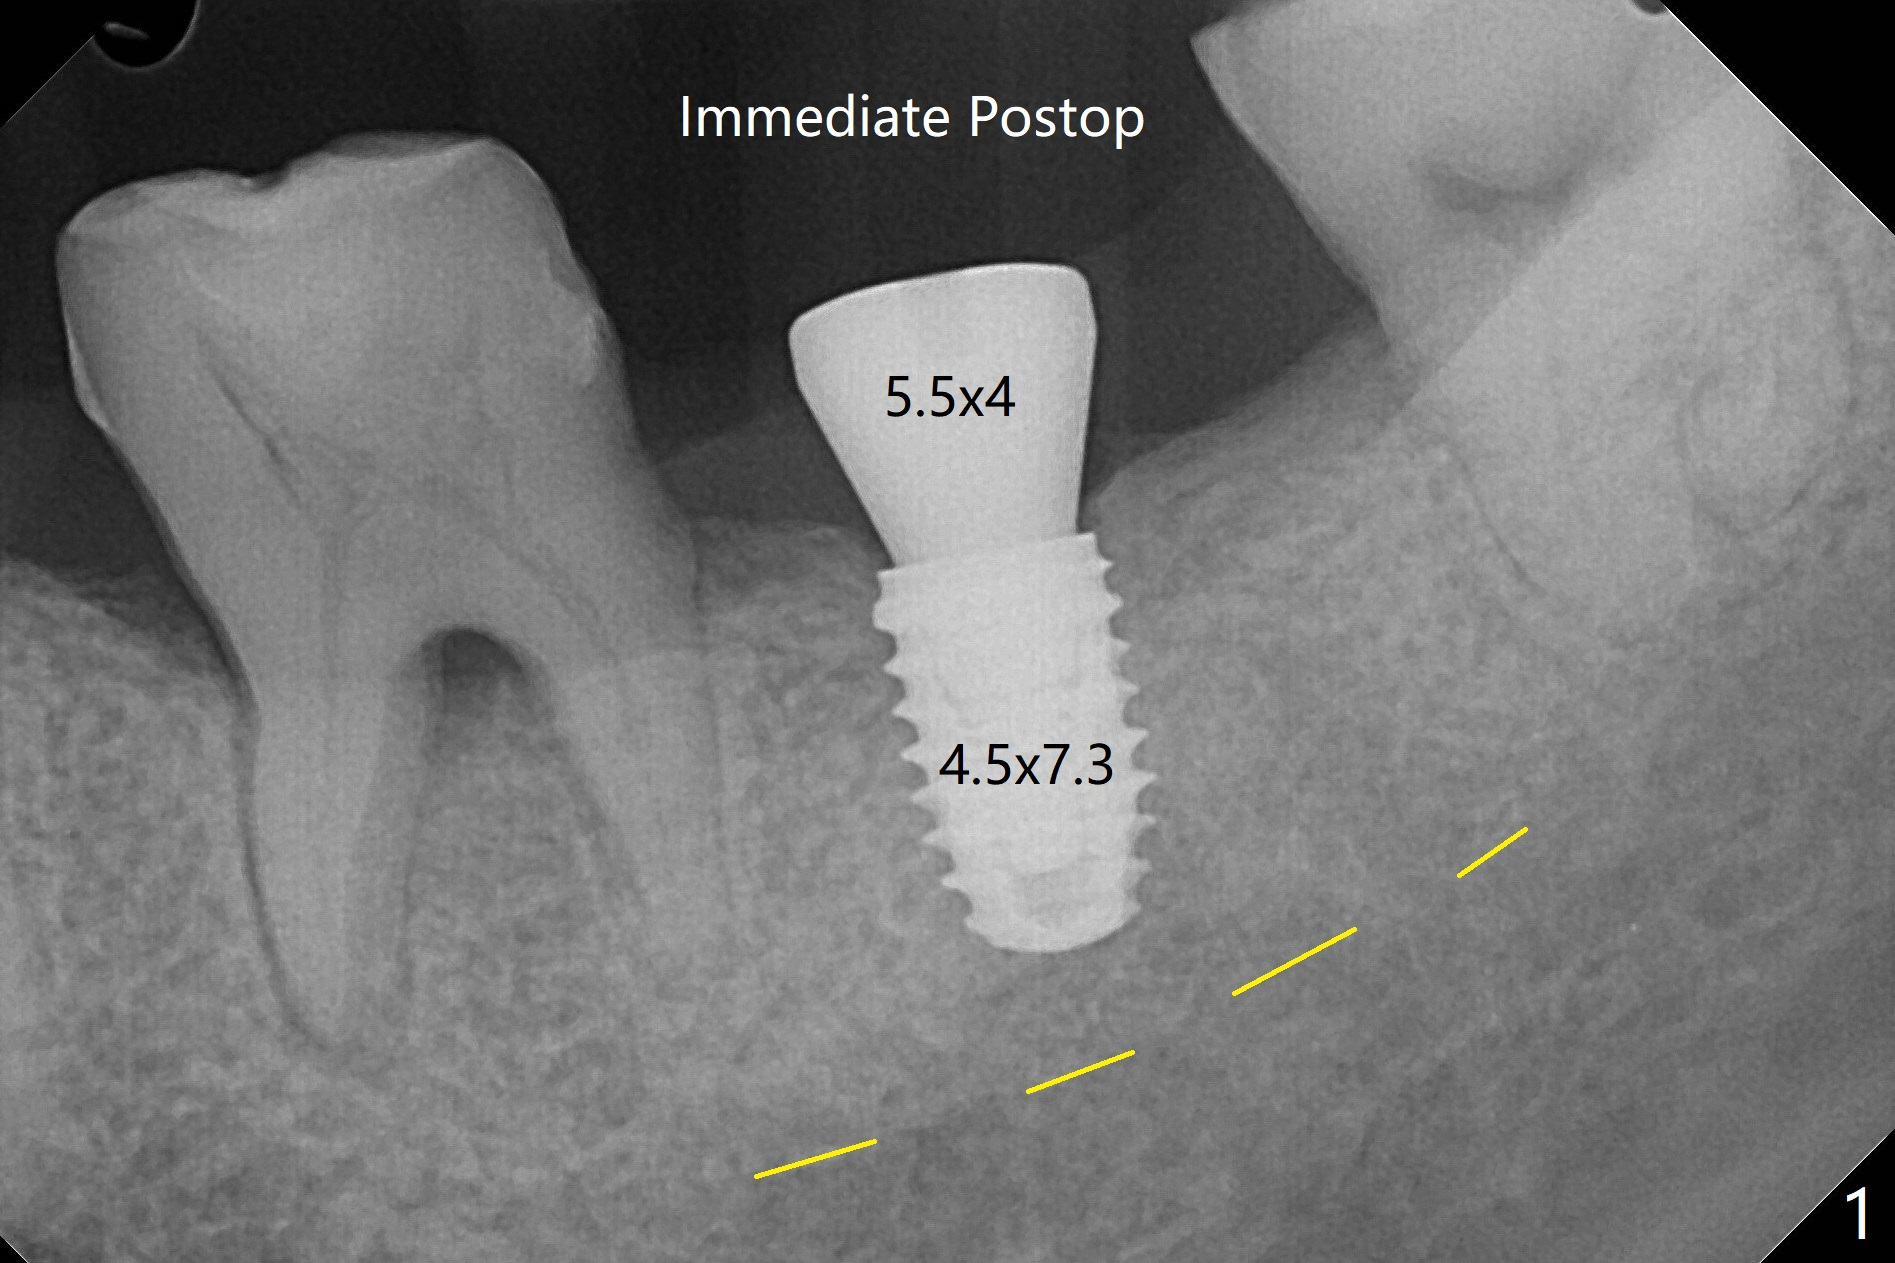

The 35-year-old woman is afraid of pain. With 34 mg of Lidocaine with 17 mcg of Epinephrine, implant placement is done with guide in a quick and painless manner (flapless, enough keratinized gingiva, Fig.1).